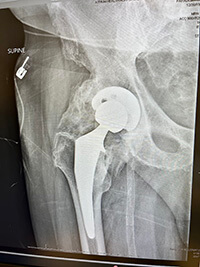

Paradise developed heterotopic ossification, a condition in which bone forms in soft tissue. Over time, the extra bone caused his hip joint to fuse, leaving him confined to a wheelchair.

On the day he turned 77, Dr. Lee and the care team performed a complex surgery at Atrium Health Lake Norman Hospital to remove the excess bone and restore movement in the joint.

“There was a significant amount of bone that had to be carefully removed while protecting the surrounding nerves and blood vessels,” Dr. Lee said. “The goal is to restore function while minimizing the risk of complications or recurrence.”